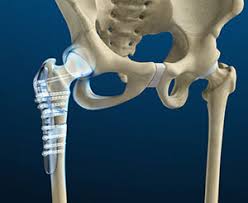

في مقالنا بعنوان "ما هي عملية رأب الفقرات؟ ما هي الحالات التي تعالجها؟ ما هي آثارها الجانبية؟"،...